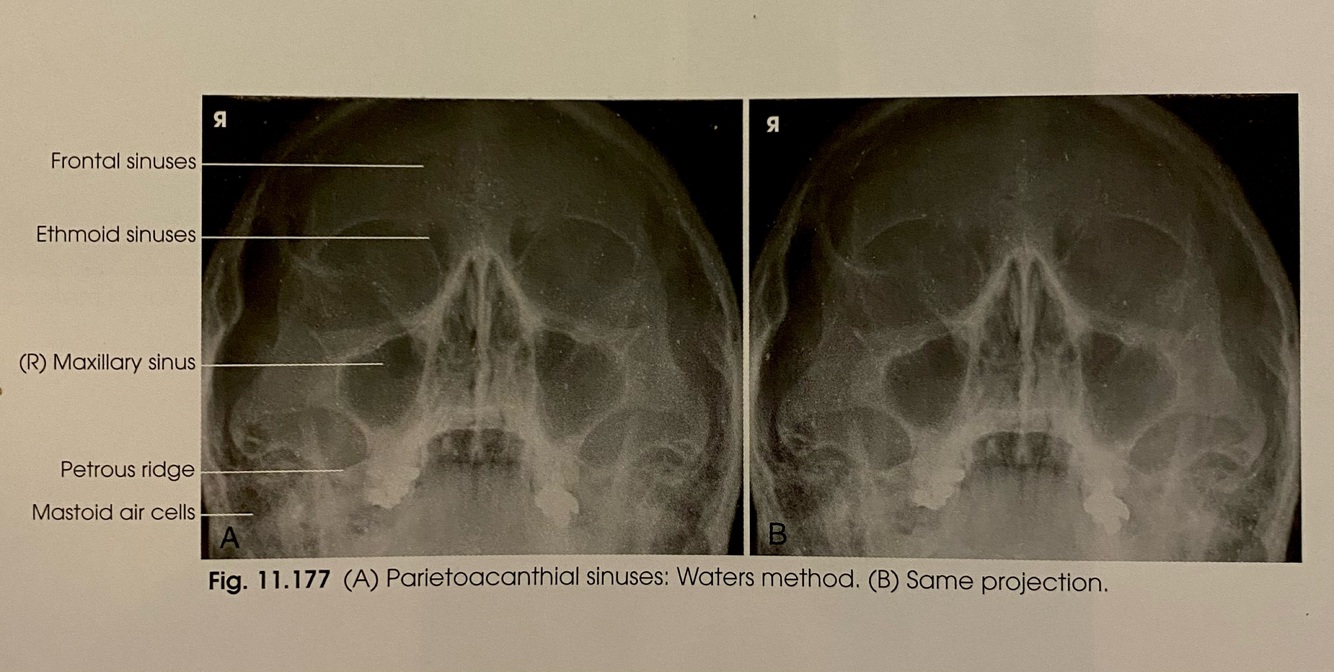

PARIETOACANTHIAL WATERS Positioning

A

-MSP is ⟂ to IR

-OML forms an angle of 37º from plane of IR

-MML is approximately ⟂ to IR

-CR: perpendicular exiting the acanthion

-Place patients chin on the grid adjusting the neck so that the MML is perpendicular to the IR

-Respiration: suspend

How well did you know this?

16

Q

PARIETALCANTHIAL WATERS Evaluation Criteria

-Proper Collimation

-Maxillary sinuses

-OML in proper position as demonstrated by:

-Petrous pyramids lying immediately inferior to the floor of the maxillary sinuses

-No rotation or tilt demonstrated by:

-Equal distances between the lateral border of the skull and the lateral border of the orbit on both sides

-Orbits and maxillary sinuses symmetric on each side

-MSP of head aligned with the long axis of collimated field

-Air fluid levels if present

Which projection shows the Maxillary sinuses?

Parietoacanthial (Waters)

What view shows the foramen rotundum